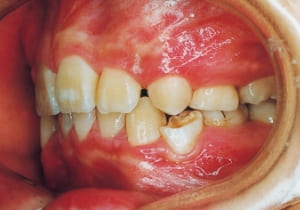

The first phase of treatment involved extracting the left and right maxillary deciduous canines. The space created was used to forcibly retract the four anterior teeth, thereby aiming to improve lip closure function (6–9, 11). Morphological changes suggest that lip function differed before and after treatment (6, 9). Subsequently, the first premolars erupted, but extraction is planned to secure space for canine eruption (10). A Class II molar relationship remains, but the significant overjet has improved (11).

In the maxilla, insufficient space for canine eruption was inevitable, necessitating extraction as part of the treatment plan. The maxillary first premolars on both sides were extracted during routine observation to create space for canine eruption (14). Eventually, the canines erupted and settled into relatively favorable positions (15,19,20). In the mandibular dentition, crowding was also present, leading to extraction of the mandibular first premolars on both sides. Treatment with full bracket was then initiated (17).